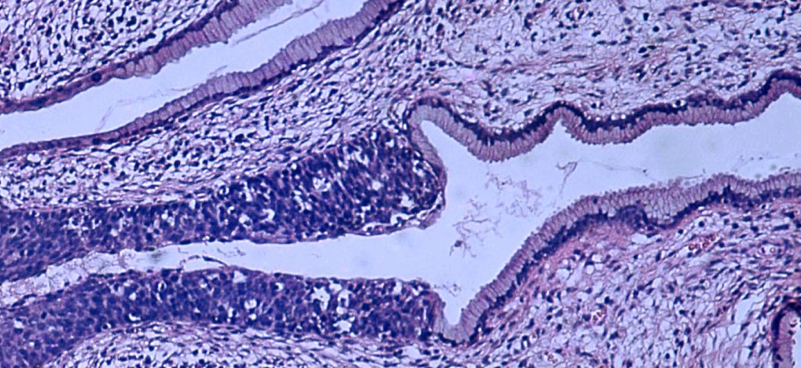

HPV is the most common sexually transmitted disease in the United States; the virus is transferable through skin-to-skin contact.

Pei and other investigators at NYU Langone Medical Center monitored the interaction between non-cancerous HPV genotypes and cancerous strains, 16 and 18, to study inherent cancer triggers.